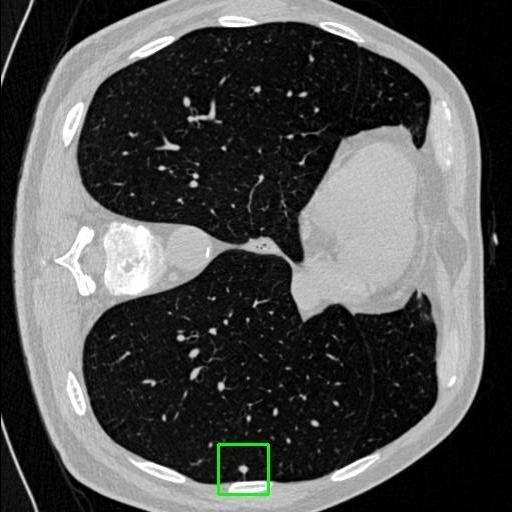

We developed an AI-based system using deep learning models for analyzing lung CT scans to detect and classify pulmonary nodules. We chose the YOLOv11 architecture for its enhanced object detection capability and adapted it specifically for medical imaging, incorporating pixel-level precision and severity classification.

Classification into three severity levels with colored bounding boxes.

Designed a severity classification system that categorizes nodules into null, moderate, and severe using colored bounding boxes, assisting in rapid clinical decision-making.